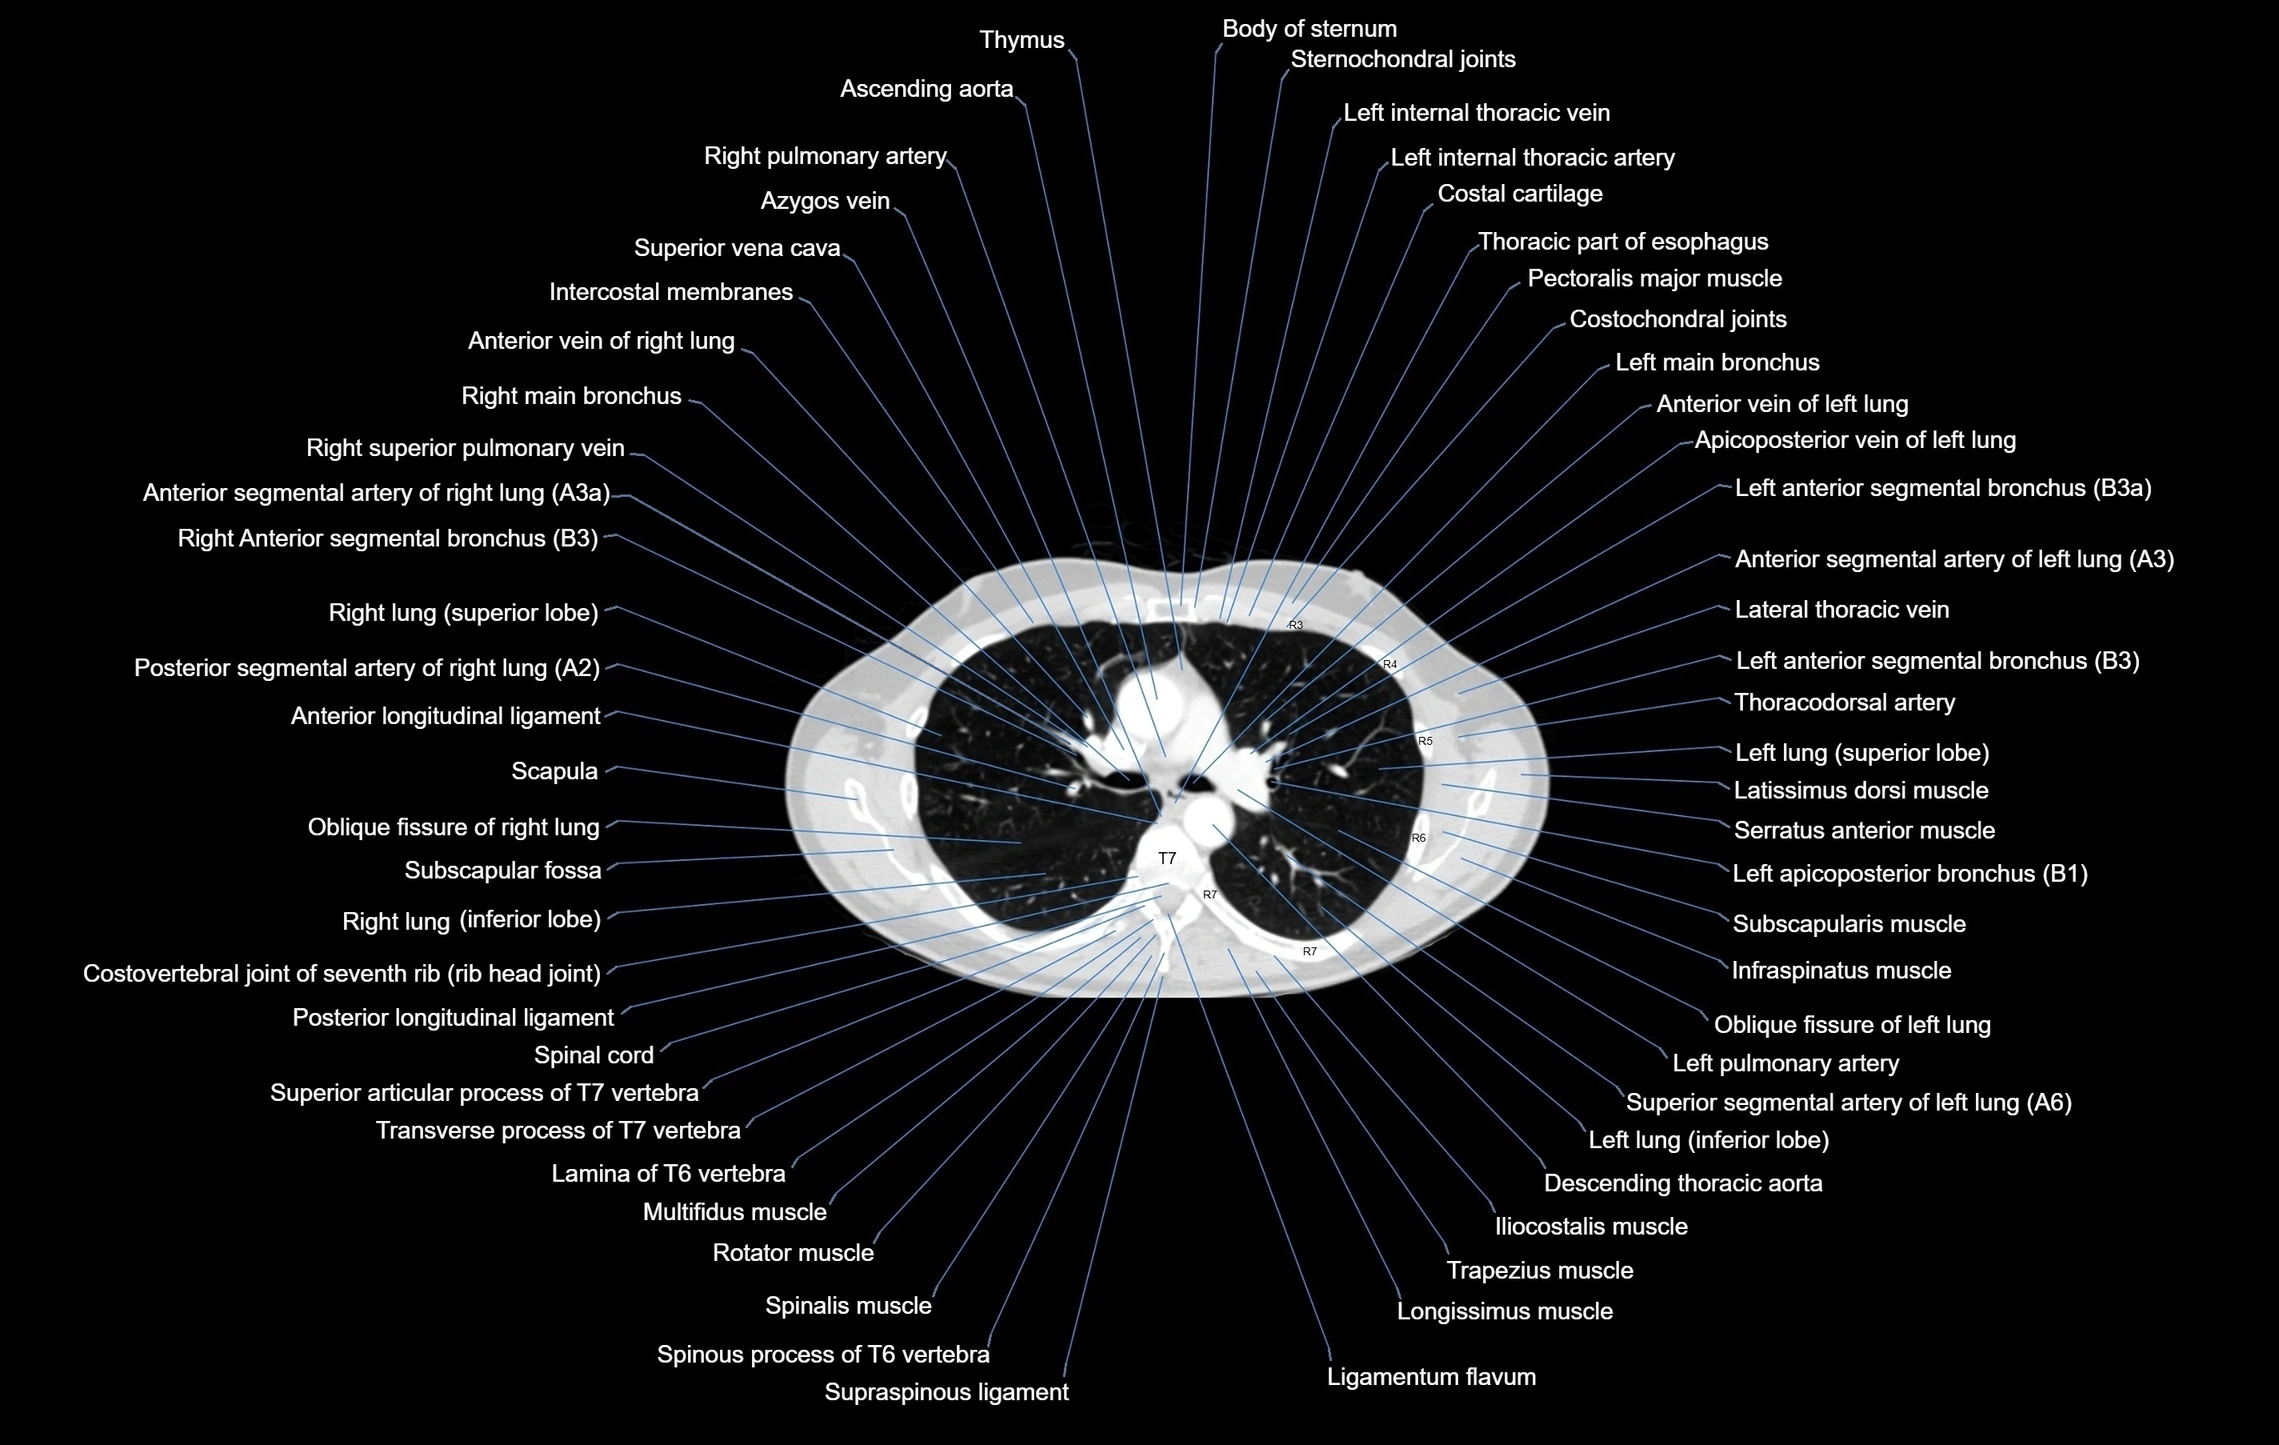

CT images